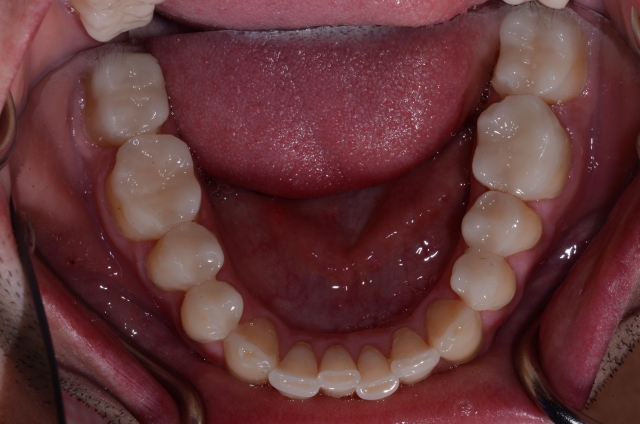

The first key to making this possible is that the teeth you’re dealing with must be smaller than the desired final size once they’re restored. This could be due to a genetic condition such as peg laterals (Fig. 1) or a case that involves excessive wear (Figs. 2–3).

In a case like this, when pretty much all the teeth are worn (yet still in the right position), you can add to them, restoring what has been worn away and at the same time adding a protective layer. Yes, you would prepare the teeth lightly to gain defined margins, but I would argue that if you pick the right restorative materials, you don’t even have to do that in this case.